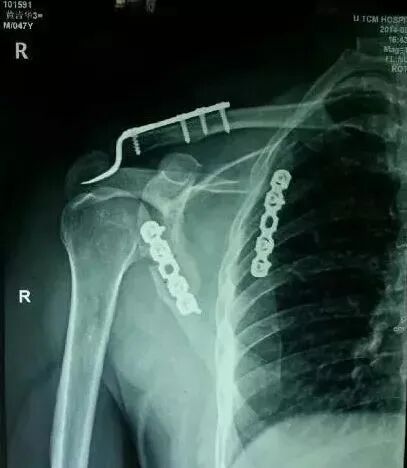

(2)肩胛带骨折

1)锁骨骨折

图片

骨折伤及锁骨下动脉,臂丛,应立即手术。

2)肩胛骨骨折

在2周之后手术,困难程度翻番。